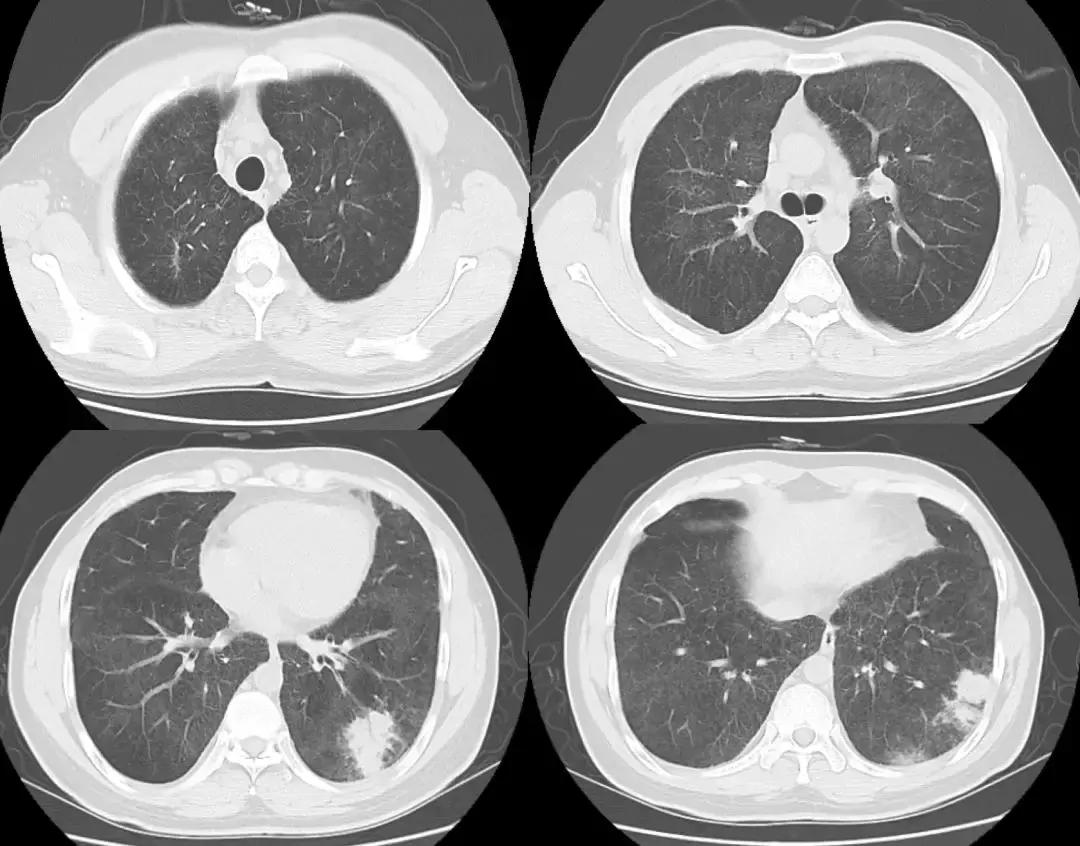

复查胸部CT(2018-07-12):

左肺炎症较前好转,但肺部弥漫性病变较前变化不大。

5、辅助检查:血常规白细胞不高、血红蛋白多次查均为170多g/L;血气分析(多次未吸氧状态):PO2 70多mmHg;血沉最高44mm/h,经治疗后可降至正常;PCT、CRP等感染相关指标均不高;病毒系列、术前四项等均阴性;于我院查自身抗体、ANCA均阴性,抗CCP抗体曾出现阳性,后复查为阴性,就诊于北京协和医院后查ANCA-IgG型 1:10为阳性、抗CCP抗体强阳性、自身抗体阴性;胸部CT提示两肺弥漫磨玻璃病变,左肺肺炎;于北京协和医院行CT引导下经皮肺穿刺术活检病理结果示:肺组织慢性炎,间质纤维组织显著增生,伴较多炎细胞浸润,可见上皮样肉芽肿伴多核巨细胞反应,未见明确坏死,PAS、抗酸、弱抗酸、六胺银染色均阴性,免疫组化CD34(血管+)、Bcl-2(散在+)、SMA(灶+)、CD68(+)、Desmin(-)。经激素治疗3月余后,左肺炎症较前好转,但肺部弥漫性病变较前变化不大。